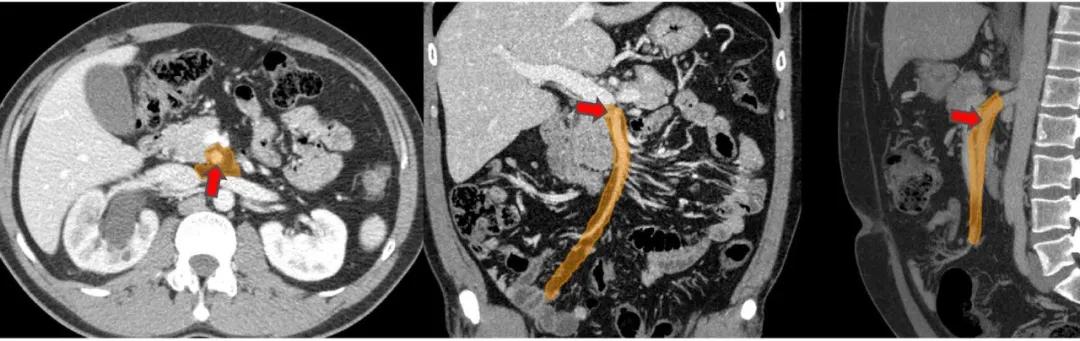

肠系膜根(橙色)。小肠系膜在肠系膜上动脉(SMA,红色箭头)的起始处有一个「肠系膜根」:小肠系膜从根区扇出,SMA 将其悬挂在后腹壁至回肠末端。